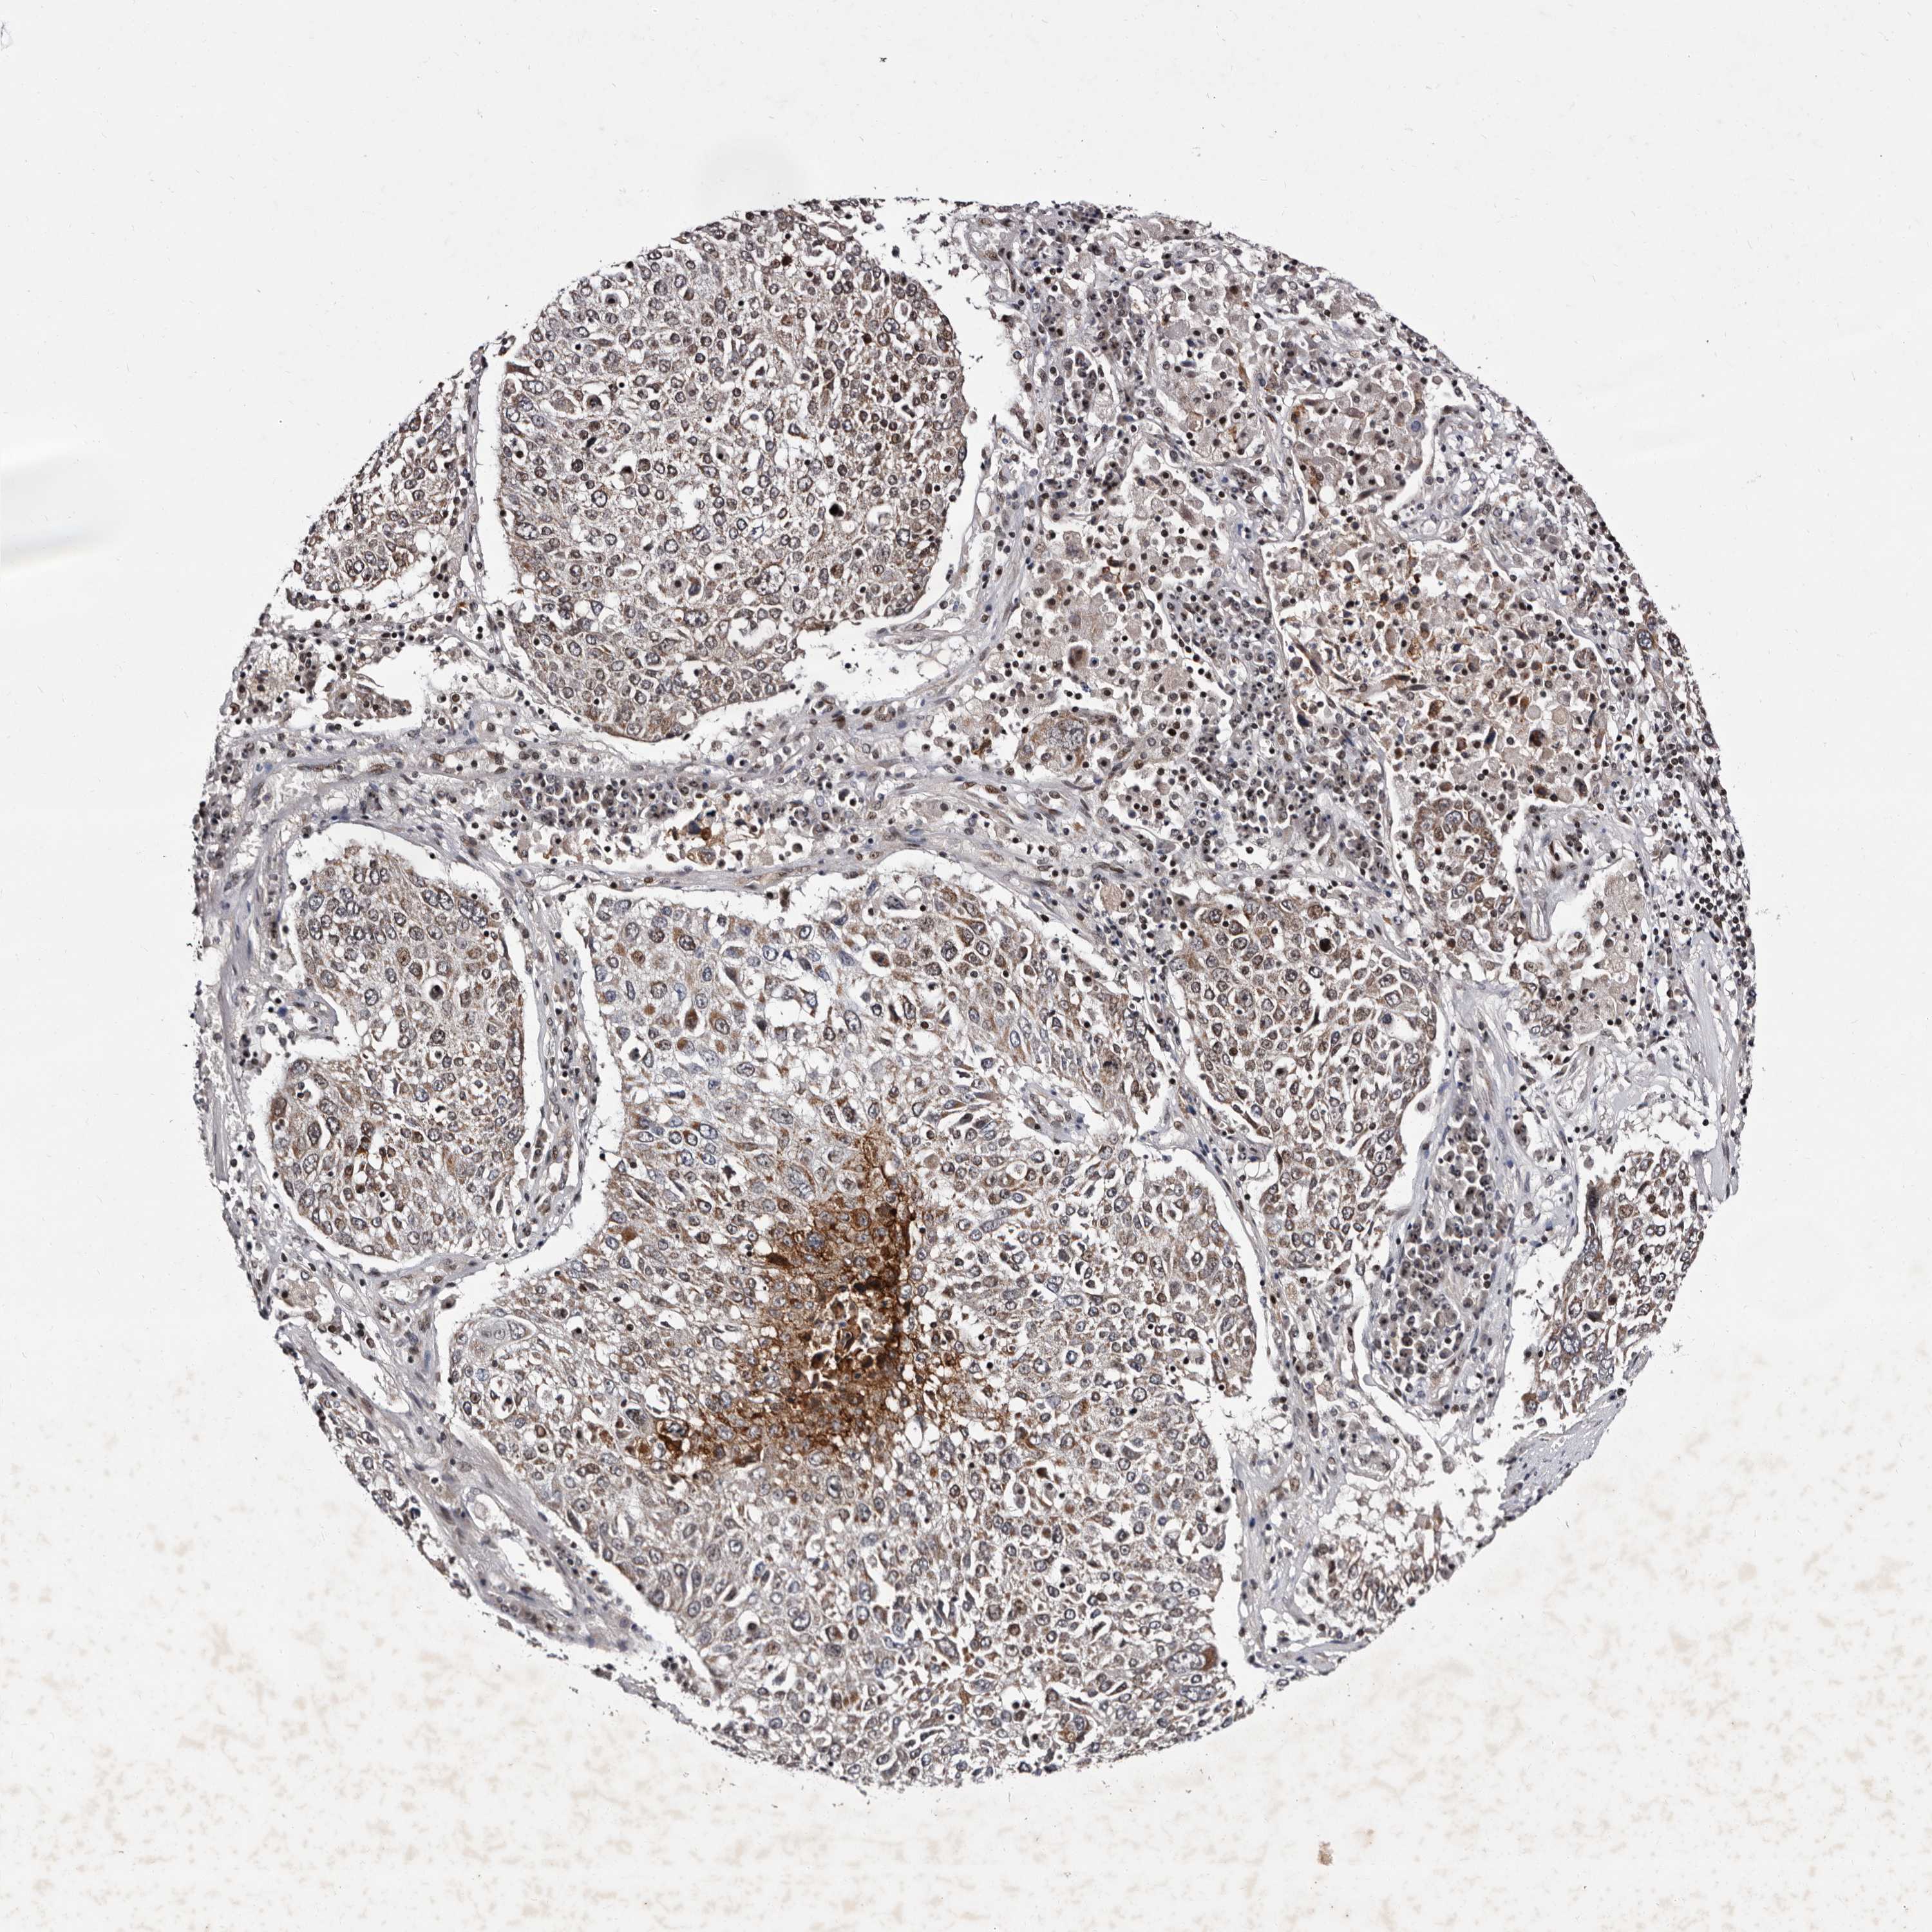

CANCER LUNG CANCER Show tissue menu

LUAD TCGA LUAD VALIDATION LUSC TCGA LUSC VALIDATION PROTEIN LUAD CPTAC PROTEIN LUSC CPTAC PROTEIN EXPRESSION